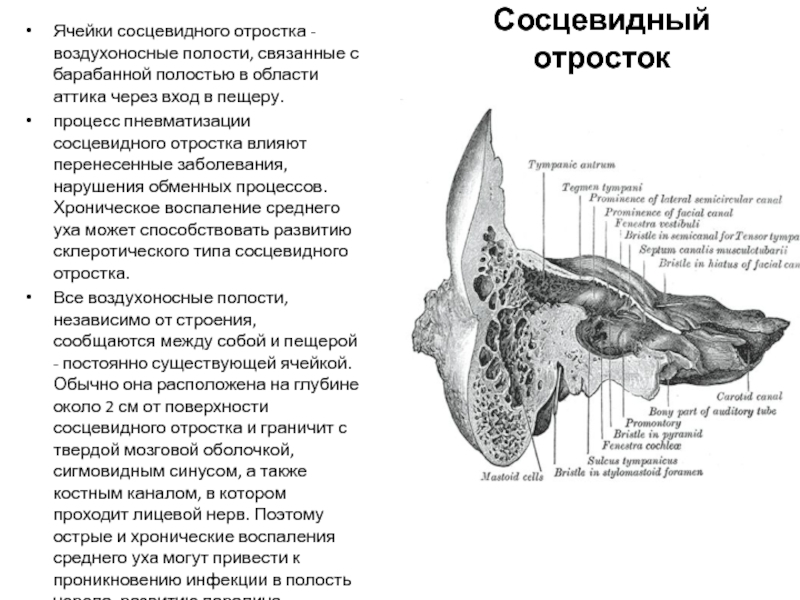

Анатомия сосцевидного отростка